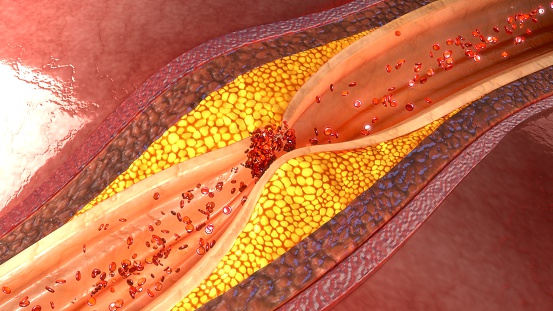

A pooled analysis of randomized trials found that moderate to severe coronary artery calcification (CAC) is associated ...

Coronary computed tomography angiography (CCTA) can detect atherosclerosis, even among individuals with no coronary ...

The results of a study show a link between the profile of serum fatty acids (FAs) and early-onset coronary artery ...